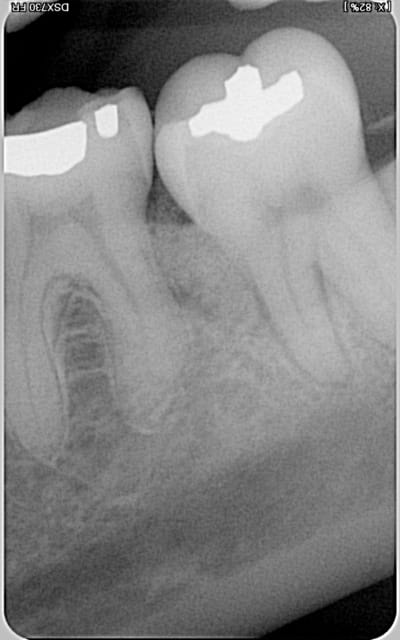

Paro ultra agressive chez une jeune femme de 30 ans.

Je te montre quelques cas cliniques traités avec Emdogain et sans matériaux de comblement sur lesquels j'ai plusieurs années de recul :

Cas 1

Initial 46 th2se3 - Eugenol

Final 46 s2gxlk - Eugenol

Cas 2 (parodontite aggressive sur une jeune fille de 13 ans)

Photos initiales c6c2bg - Eugenol

Bilan initial nhvmno - Eugenol

Photos  1an drrxtl - Eugenol

Comparaison bilan rx bix6qa - Eugenol

Bilan de sondage  1 an muiwyr - Eugenol